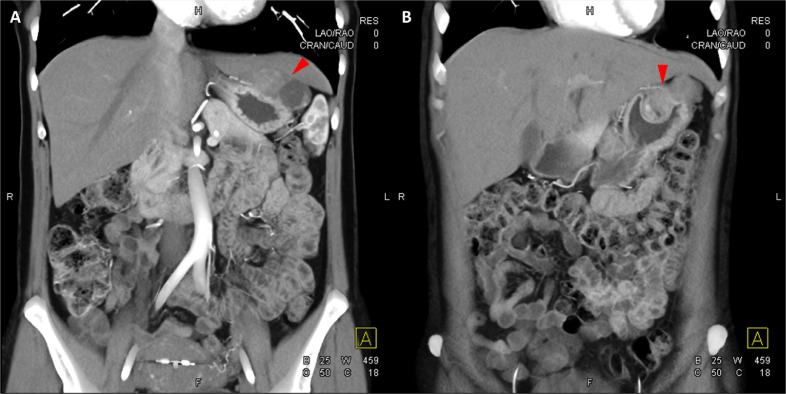

Fig. 3

圖 3:多個(gè)胃腸道間質(zhì)瘤的冠狀和矢狀圖像。 (A 和 B)冠狀動脈相對比增強(qiáng) CT 圖像顯示胃賁門產(chǎn)生的外生性腫塊。 (C 和 D)矢狀動脈相位對比增強(qiáng)圖像顯示腫塊的異質(zhì)性和外生結(jié)構(gòu)。

Fig. 4

圖 4: 胃腸道間質(zhì)瘤的三維表示。 (A 和 B)胃腸道間質(zhì)瘤在動脈期和冠狀面的 3D 可視化提供了進(jìn)一步的解剖細(xì)節(jié)和空間信息。